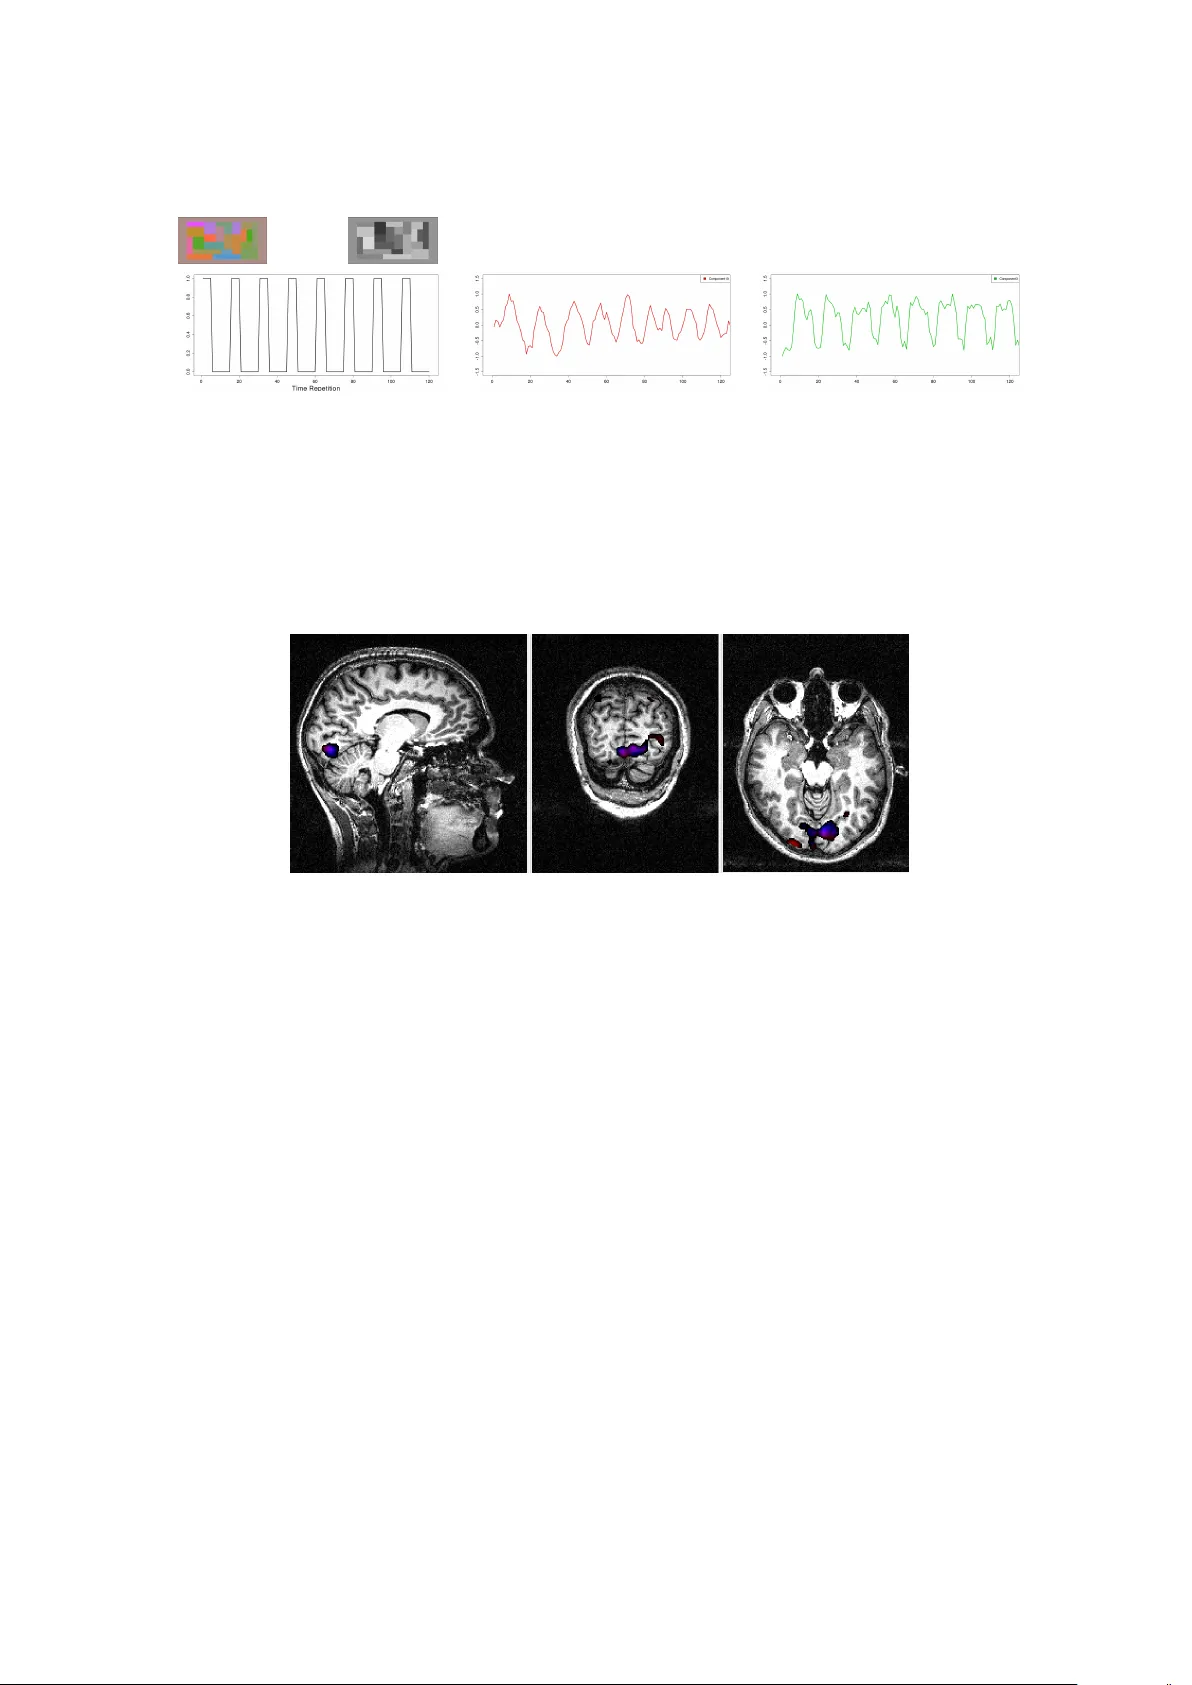

실험에서는 (1) 잡음이 섞인 합성 데이터에서 알려진 독립 소스를 정확히 복원함을 확인하고, (2) 인간 시각 과제 fMRI 데이터에 대해 전뇌 tICA를 적용해 시각 피질 및 연관 네트워크를 시간적 독립 성분으로 분리하였다. 결과는 기존 sICA와 비교해 시간적 해상도가 높은 독립 성분을 제공함을 보여준다. 또한, 패키지의 시각화 도구를 통해 각 성분의 공간적 패턴과 시간적 활성 곡선을 직관적으로 탐색할 수 있다.